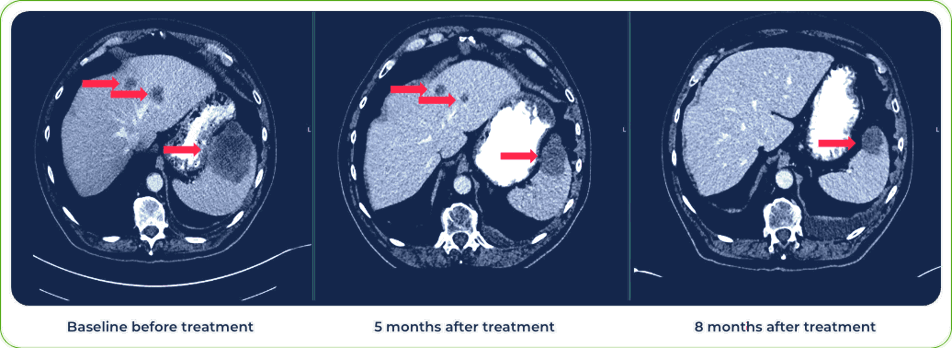

Stage IV Squamous Cell Carcinoma of Lung

Sites of metastases:

Spleen and liver